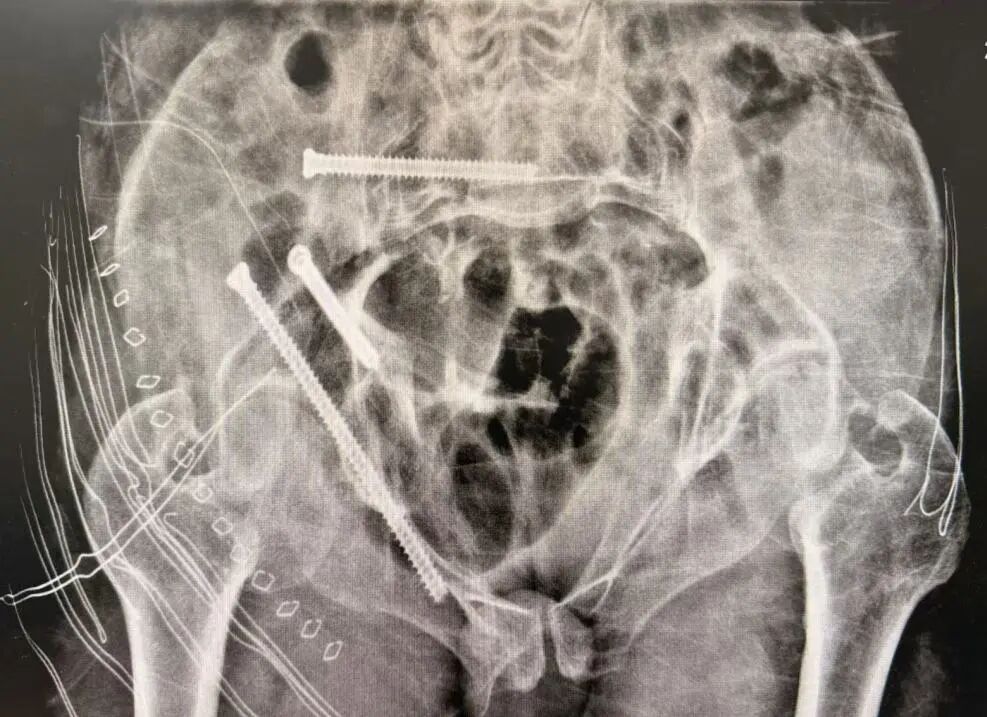

此次接受手术的七旬老人,因干活时不慎从自驾车摔落,导致全身多部位骨折,其中包括胸椎压缩性骨折、腰椎压缩性骨折、髂骨骨折、骶骨骨折、尾骨骨折、耻骨骨折、坐骨骨折。因骨盆结构复杂、周围血管神经密集,骨盆骨折素有“创伤之王”之称。面对患者骨盆多处骨折、血红蛋白偏低、传统手术可能带来较大创伤和出血风险等难题,贾长军主任团队果断选择借助最新引进的骨科手术机器人,制定个性化微创手术方案。

团队通过三维影像重建,为患者量身定制手术路径,数据导入系统后生成个性化复位方案。

机械臂按预设路径自动执行复位操作,精度高达毫米级,医生仅需通过几个微小切口置入内固定螺钉。

术后患者恢复迅速,第二天已能下床站立。整个过程真正做到了“快、准、稳”,极大提升了手术安全性与疗效可控性。